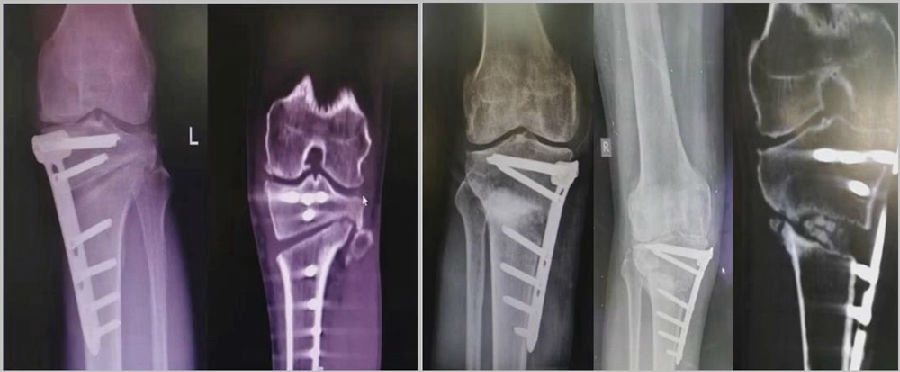

拉力钉复位,结构性植骨

左侧患者未植骨正常负重,术后4个月不愈合;右侧患者非结构性植骨过早负重,术后1年未愈合

2、处理

(1)如果在手术台上,或是刚做完手术就发现矫正不良问题,此时比较简单。需要先跟患者进行沟通,在手术中直接将远端4颗螺钉卸下来,调整好力线后重新打入即可。但是注意要把远端单皮质螺钉换成双皮质螺钉。

(2)如果患者已经达到初始愈合,此时如果出现过度外翻,需要在内侧重新做内侧闭合楔。